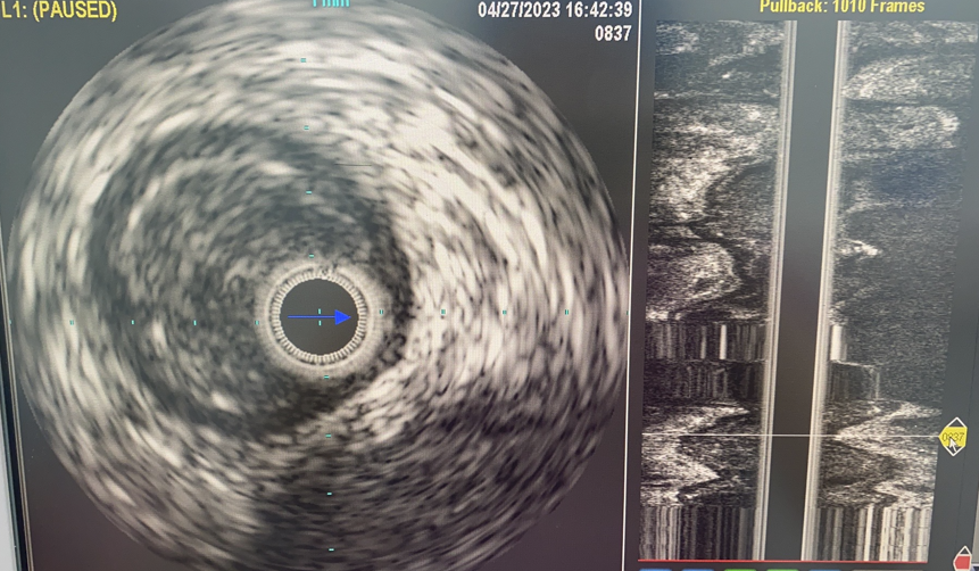

确认导丝位置

在CTO病变开通过程中,导丝可能位于真腔、内膜下甚至中膜层。DSA有时难以准确判断。IVUS可以明确导丝的位置,这对于后续治疗策略有决定性影响。若导丝位于内膜下,贸然使用Rotarex等减容装置可能引发血管穿孔等严重并发症。而确认真腔通过后,方可安全进行后续操作。

病例1(股腘动脉CTO):

一例重度间歇性跛行患者,导丝通过股腘动脉CTO病变后,若仅凭DSA判断,可能直接进行Rotarex减容。但IVUS检查发现导丝实际位于内膜下(假腔)。此时若进行减容,风险极高。术者遂调整策略,改用球囊扩张后植入Viabahn支架,成功避免了严重并发症。